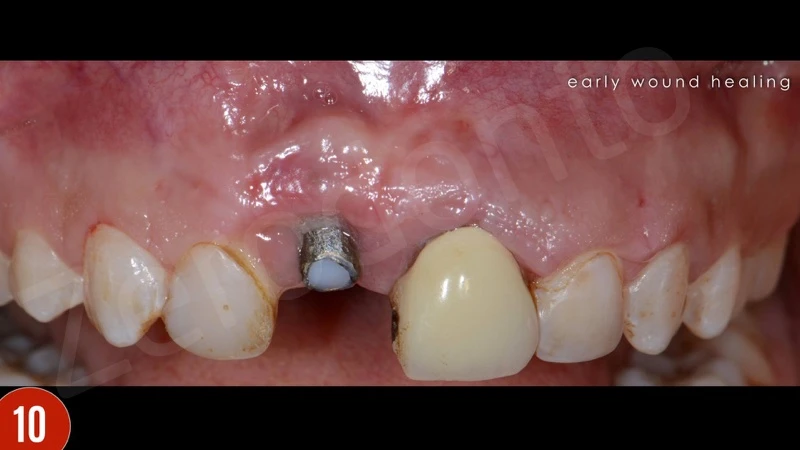

Sau khi gây tê tại chỗ, răng giả đã được cắt và loại bỏ. Sau đó, xương ổ răng vẫn hiện diện quanh implantl. Trong lần điều trị này, điều chỉnh chính xác abutment được thực hiện và xác nhận với X-quang. Khu vực cấy implant được để lành thương mô mềm. Sau 8 tuần lành thương mô mềm, phẫu thuật ghép mô liên kết (CTG) đã được lên kế hoạch với vạt bao, vạt nhú lợi xoay xiên (oblique rotated papilla flap) bằng cách sử dụng các đường rạch dưới lợi viền. Kĩ thuật chia tách tạo khả năng di động thích hợp cho vạt niêm mạc. Các phần lợi viền phía cổ được loại bỏ. CTG được lấy bằng kỹ thuật loại bỏ biểu mô. Để bù đắp thiếu hụt niêm mạc, CTG được gấp đôi và khâu bằng với vật liệu tự tiêu trước khi khâu cố định. CTG đã được cố định mặt môi, ôm lấy bề mặt abutment. Vạt niêm mạc tự do, thụ động, căng được khâu.

Sự lành thương sớm và tăng độ dày niêm mạc phía môi là thích hợp. Ba tháng sau khi phẫu thuật nha chu, bệnh nhân báo cáo có lỗ rò ở vùng đỉnh răng 21. Đo độ sâu thăm khám là 2-3 mm. Do răng không vừa khít, và lực nhai quá mức, một gãy xương ở vùng chóp đã gặp phải. Bệnh nhân được giải thích cần nhổ răng. Bệnh nhân đã quyết định cấy ghép tức thì.